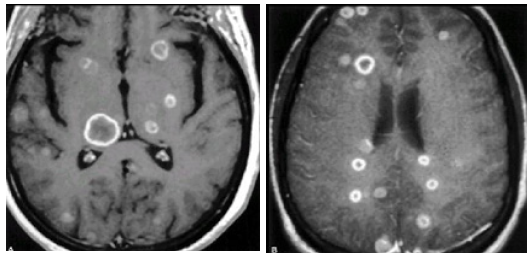

Sign: They are summarized in (Table 8 & Table 9 ). CT Scan: This was done for all the patients, 9 of them without I.V contrast, and 16 of them with I.V. contrast enhancement. Ten patients (40%) have single brain metastases, and 15 patients (60%) have multiple brain metastases Fig.(3.6) .In the 10 patients having single brain metastasis, the location [24,25] of the metastasis in relation to the brain was shown in (Table 10 ) and the relation of the primary origin of the tumor to multiplicity is seen in (Table 11 ). The density of the tumors was variable. 21 patients (84%) have solid tumors, and 4 patients (16%) have a cystic component of the tumor . The density of the solid tumors was isodense in 9 patients, hypodense in 7 patients, mixed density in 2 patients, and hyperdense in 3 patients

Enhancement of the tumor was seen in all the 16 patients in whom an I. V. contrast was used. 6 patients (37.5 %) showed ring like enhancement and 10 patients (62.5 %) showed heterogeneous enhancement.Perifocal edema was noticed in all the cases. It was marked in 6 patients (24 %), moderate in 15 patients (60%), and mild in 4 patients (16%). The metastases were supratentorial in 14 patients (56 %), infratentorial in 5 patients (20%), and both supraand [26,27,28] infratentorial in 6 patients (24%). Hydrocephalus was seen in 5 patients (20%), all of them have an infratentorial brain metastasis. It was due to compression of the 4thventricle by the metastasis leading to dilatation of the lateral and 3rd ventricles (triventricular hydrocephalus) (Figure 6 ).

MRI: This was done for only 11 cases according the availability of this study in these hospitals. T1 and T2 studies done for all of those taken the MRI study but Gadolinium contrast study done for only 5 of those cases. (Figure 7& Figure 8 ) Brain MRI T1 and T2 studies